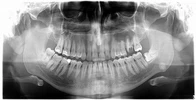

Dt. Leyla Devrez Diş Hekimi

Diş hekim